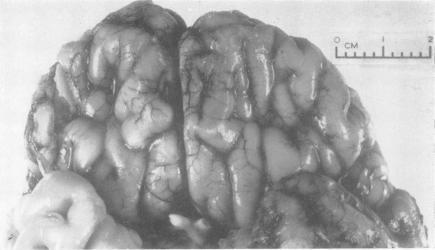

A PROBABLE CASE OF INCOMPLETE TRISOMY OF A CHROMOSOME OF THE 13-15 GROUP.

J Med Genet. 1965 Jun;2(2):136-41. doi: 10.1136/jmg.2.2.136.